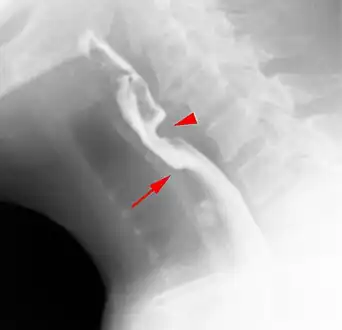

Web with "jet-phenomenon". Arrowhead on incomplete opening of the upper esophageal sphincter.

The diagnostic test of choice is a barium swallow.